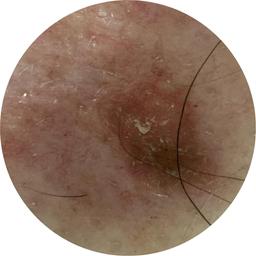

ISIC_8917580

diagnosis_1 Benign

diagnosis_confirm_type single image expert consensus

image_type dermoscopic

lesion_id IL_4139461